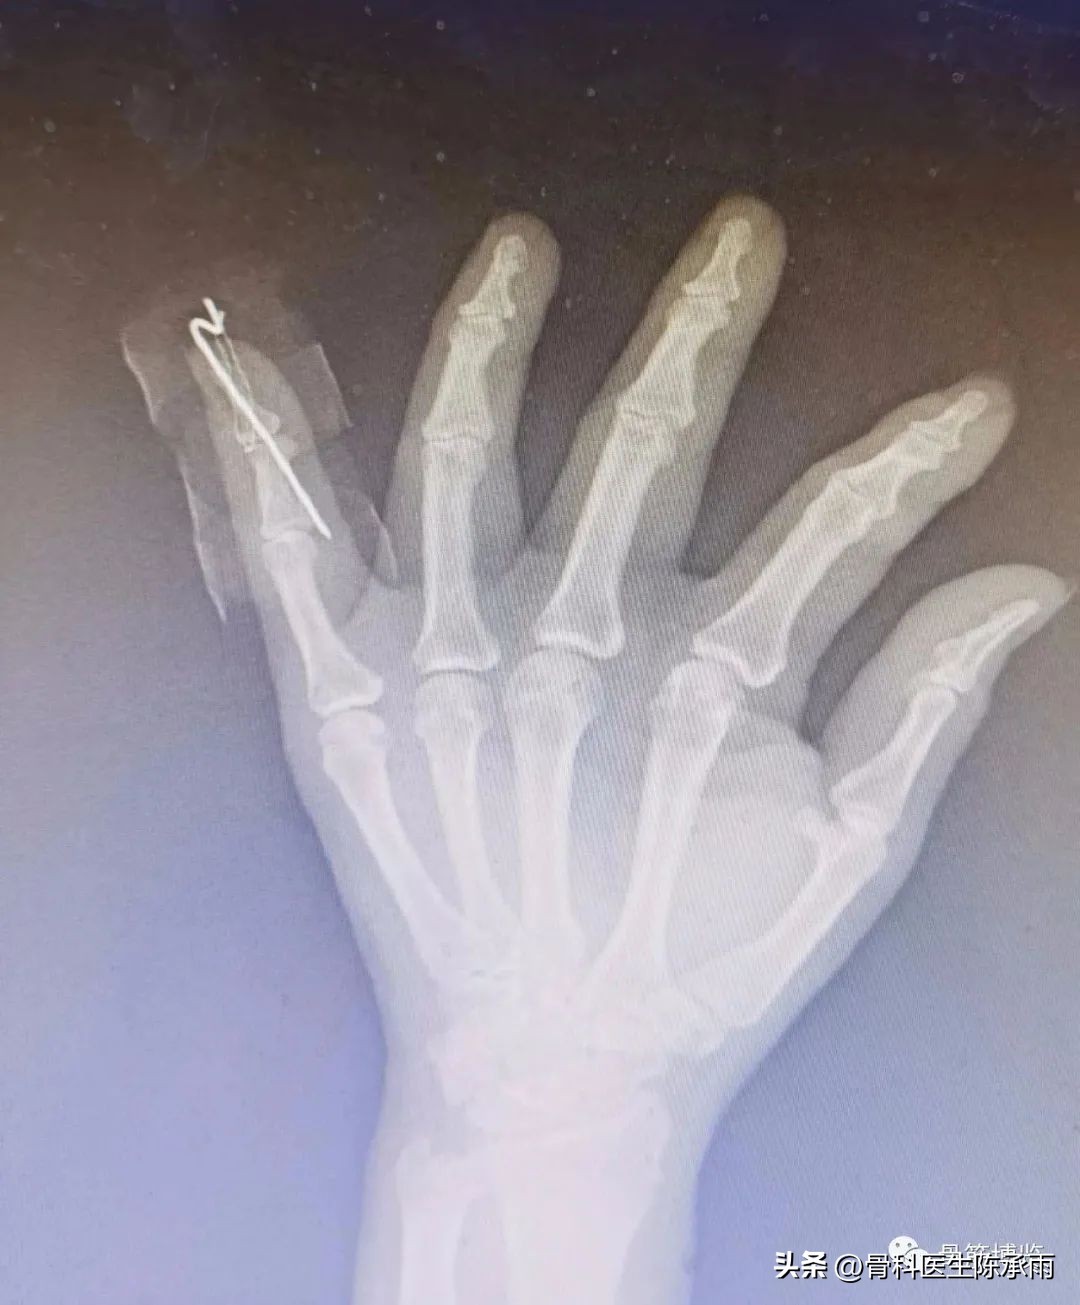

(1)经皮(不切口)背侧阻挡钉手术固定,缺点是仍有部分旋转不能矫正

(2)钢丝抽出指腹侧钮扣加克氏针固定或直接固定于克氏针上

(3)锚钉固定克氏针固定

一般固定6周后去除外固定或拔除克氏针及钢丝,逐步进行手指功能锻炼。